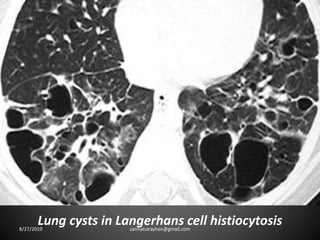

Cystic lung disease:

-Lung cyst is radiolucent area with a wall thickness

of less than 4mm.

8/27/2019 zannatulrayhan@gmail.com

Lung cysts in Langerhans cell histiocytosis8/27/2019 zannatulrayhan@gmail.com